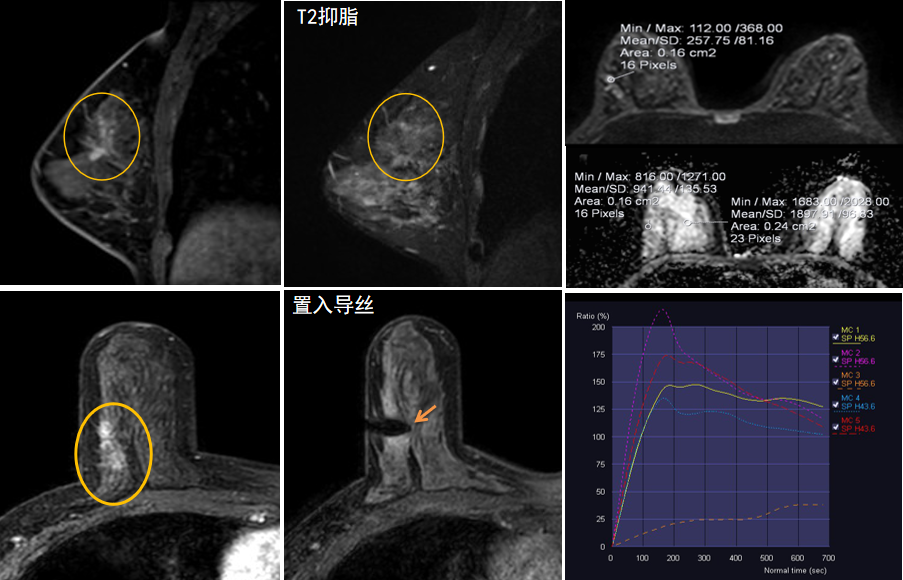

今年45歲的某女士,兩個月前行超聲檢查發(fā)現(xiàn)右乳結(jié)節(jié),乳腺X線攝影檢查提示右乳外上象限局部腺體結(jié)構(gòu)扭曲并簇狀無定形鈣化,為了進(jìn)一步評估病變性質(zhì)并確定范圍進(jìn)行了乳腺M(fèi)R平掃 DWI 增強(qiáng)的檢查,經(jīng)MR評估發(fā)現(xiàn)右乳病變范圍較廣,評估為BI-RADS 4類可疑病變,需要取得病理學(xué)結(jié)果。

只能借助影像學(xué)引導(dǎo),但超聲僅顯示了病變中的小結(jié)節(jié),X線攝影(鉬靶)顯示的病變邊界比較模糊,要想做到精準(zhǔn)完整切除必須借助MR的引導(dǎo),而這一技術(shù)對軟硬件平臺及人員技術(shù)都有很高的要求,因此,多年來一直是我國乳腺病變診療的盲區(qū),經(jīng)常是MR發(fā)現(xiàn)可疑病變但卻無法處理。目前全國僅有少數(shù)幾家醫(yī)院開展了這方面的部分工作。

陳寶瑩主任及其帶領(lǐng)的MR介入診療小組詳細(xì)詢問了病情,分析了患者資料,并與患者和臨床醫(yī)生進(jìn)行了充分溝通,確定于手術(shù)前為患者實(shí)施MR引導(dǎo)下的病變穿刺導(dǎo)絲定位和體表范圍確定。手術(shù)前陳寶瑩主任帶領(lǐng)聶品醫(yī)師、馬小偉技師、韓愛萍護(hù)士長等MR介入診療小組成員,借助MR高清的圖像顯示和定位系統(tǒng),確定病變范圍,精準(zhǔn)穿刺置入定位導(dǎo)絲,并準(zhǔn)確標(biāo)記出病變體表范圍,整個過程患者無任何不適。在定位導(dǎo)絲和體表范圍標(biāo)記的輔助下,甲乳外科劉曉敏主任精準(zhǔn)切除了病變,解除了患者的后顧之憂。

國內(nèi)外指南均建議40歲以上的女性每年行一次雙乳X線攝影(鉬靶)檢查,以篩查乳腺癌。對于乳腺癌高危人群40歲以前即建議開始乳腺癌篩查,除了進(jìn)行乳腺X線攝影(鉬靶)篩查外需要補(bǔ)充MR檢查,MR檢查敏感性最高,能夠發(fā)現(xiàn)大量X線攝影和超聲檢查陰性的可疑病變,基于多模態(tài)、多參數(shù)的結(jié)構(gòu)和功能成像的基礎(chǔ)上,MR能夠精準(zhǔn)顯示病變位置、范圍以及病變內(nèi)的活性區(qū)域,MR引導(dǎo)下的介入診療不但解決了僅在MR顯示的病變的處置難題,而且能夠精準(zhǔn)定位活性區(qū)域,保證了定位、活檢及旋切的準(zhǔn)確性。